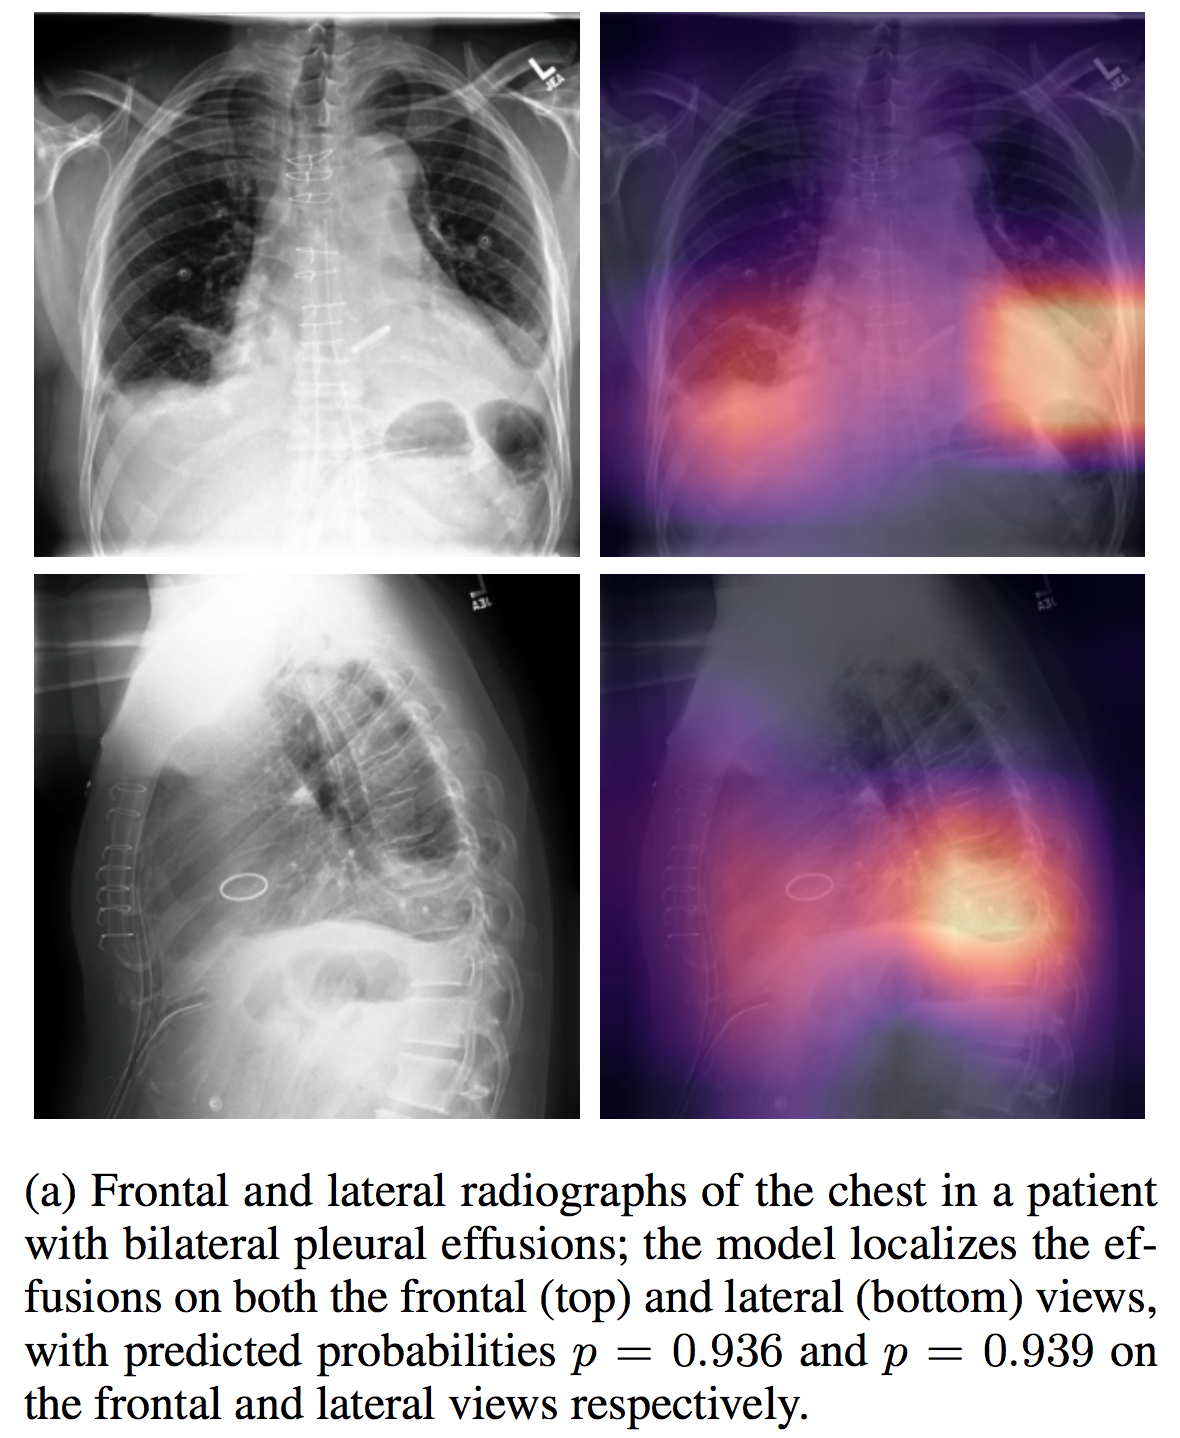

## CheXpert

| [CheXpert](https://stanfordmlgroup.github.io/competitions/chexpert/) | | | | | | | [Other](https://stanfordmlgroup.github.io/competitions/chexpert/) |

介绍论文: [CheXpert: A Large Chest Radiograph Dataset with Uncertainty Labels and Expert Comparison](https://arxiv.org/abs/1901.07031)